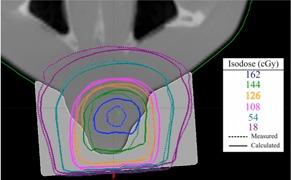

The purpose of this paper is to demonstrate that an inexpensive 3D printer can be used to manufacture patient-specific bolus for external beam therapy, and to show we can accurately model this printed bolus in our treatment planning system for accurate treatment delivery. Percent depth-dose measurements and tissue maximum ratios were used to determine the characteristics of the printing materials, acrylonitrile butadiene styrene and polylactic acid, as bolus material with physical density of 1.04 and 1.2 g/cm3, and electron density of 3.38 × 10²³ electrons/cm3 and 3.80 × 10²³ electrons/ cm3, respectively. Dose plane comparisons using Gafchromic EBT2 film and the RANDO phantom were used to verify accurate treatment planning. We accurately modeled a printing material in Eclipse treatment planning system, assigning it a Hounsfield unit of 260. We were also able to verify accurate treatment planning using gamma analysis for dose plane comparisons. With gamma criteria of 5% dose difference and 2 mm DTA, we were able to have 86.5% points passing, and with gamma criteria of 5% dose difference and 3 mm DTA, we were able to have 95% points passing. We were able to create a patient-specific bolus using an inexpensive 3D printer and model it in our treatment planning system for accurate treatment delivery.

本文的目的是证明一台低成本的3D打印机可用于制造适用于外照射治疗的个体化组织等效填充物,并表明我们能够在治疗计划系统中精确模拟这种打印的填充物,以实现精确的治疗实施。使用百分深度剂量测量和组织最大剂量比来确定打印材料丙烯腈-丁二烯-苯乙烯(ABS)和聚乳酸(PLA)作为填充物材料的特性,其物理密度分别为1.04 g/cm³和1.2 g/cm³,电子密度分别为3.38×10²³电子/cm³和3.80×10²³电子/cm³。使用Gafchromic EBT2胶片和RANDO体模进行剂量平面比较,以验证精确的治疗计划。我们在Eclipse治疗计划系统中精确模拟了一种打印材料,为其赋予260的Hounsfield单位。我们还能够使用伽马分析进行剂量平面比较来验证精确的治疗计划。在伽马标准为5%剂量差异和2 mm剂量-距离容差(DTA)的情况下,我们能够使86.5%的点通过;在伽马标准为5%剂量差异和3 mm DTA的情况下,我们能够使95%的点通过。我们能够使用一台低成本的3D打印机创建个体化组织等效填充物,并在我们的治疗计划系统中对其进行模拟,以实现精确的治疗实施。